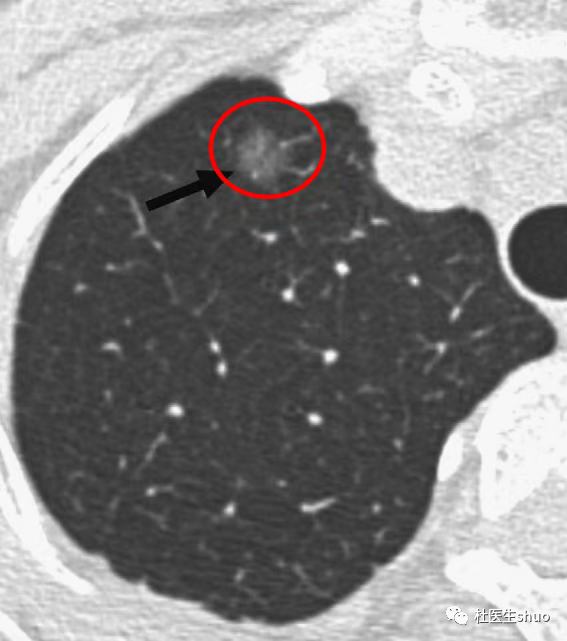

结合术前影像学检查来看,如果术前CT是纯磨玻璃结节,有一篇2023年发表在《Ann Thorac Surg》的研究,题目为《纯磨玻璃样腺癌手术后10年随访结果》。

研究共纳入308例纯GGO特征的肺腺癌患者。其中226例(73.4%)为女性,268例(87.0%)为非吸烟者,187例(60.7%)接受了亚肺叶切除术。

这些患者的10年无复发生存率为100%,10年总生存率为96.9%。

5年和10年肺癌特异性生存率均为100%。

即使病理学诊断为浸润性腺癌,手术后10年,纯GGO特征的肺腺癌也未见复发。纯GGO可以通过手术治愈。

研究强调,放射学表现为纯GGO的肺腺癌应与其他肺腺癌相区分。